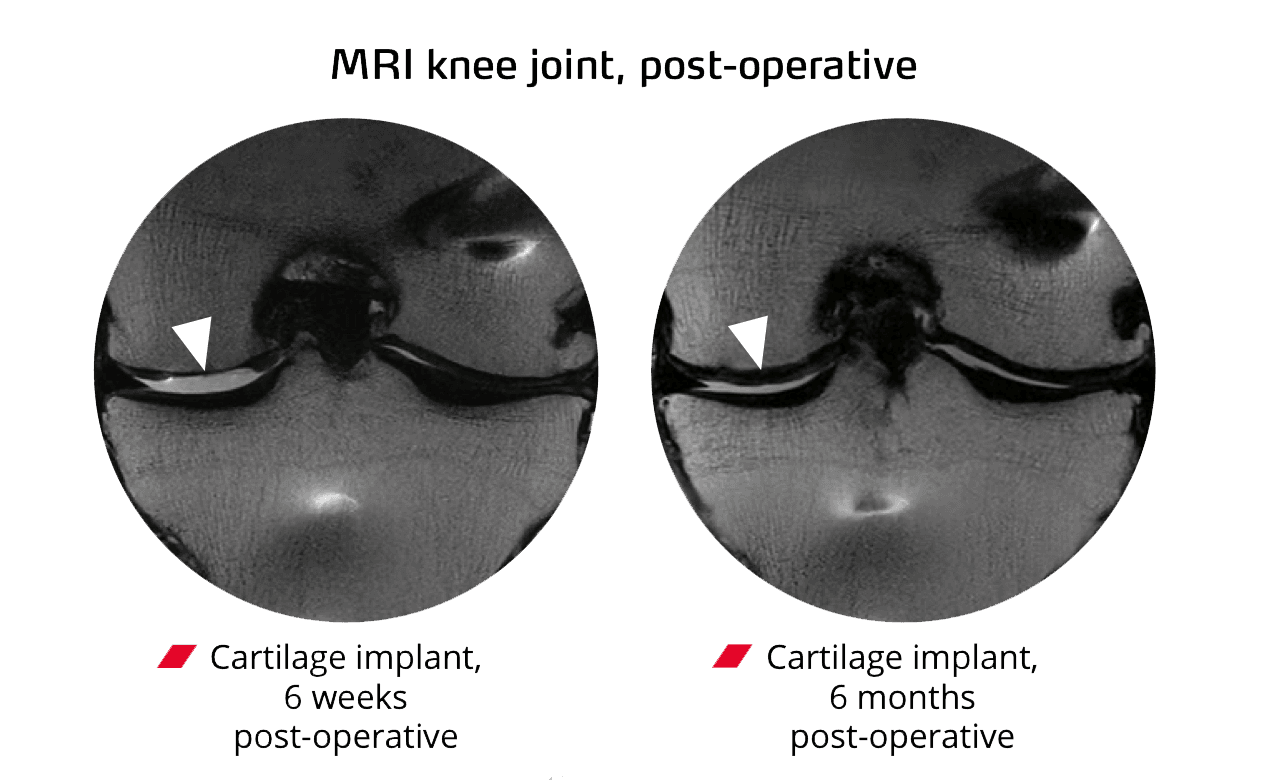

Studies show +30 IKDC in knees,+33 Harris Hip Score in hips, and improved ankle metrics. MRI (MOCART) typically reads 70–87. Globally,>19,000 cases support safety and function.

Delivered via precise injection orkeyhole surgery. The gel sets in minutes. Expectpartial weight-bearing ~6 weeks, steady return to cycling/swimming, and most sports around~12 months alongside specialist rehab.